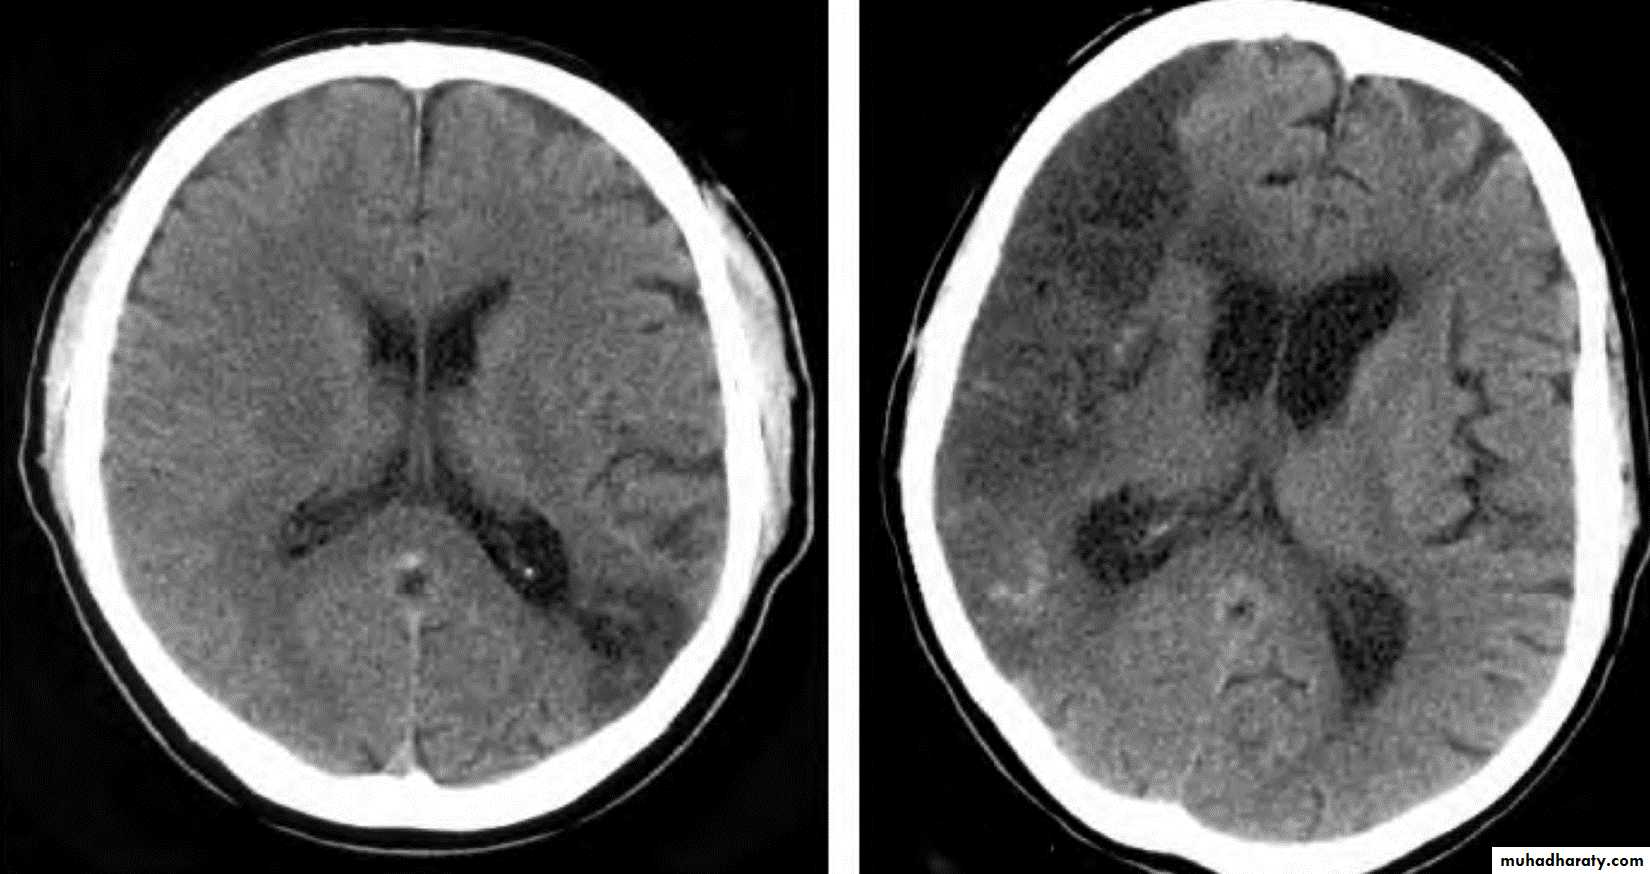

• Role of CT and MR in patients with stroke• Early CT and MR signs of infarction

• Exclude hemorrhage• Differentiate between irreversibly affected brain tissue and reversibly impaired tissue (dead tissue versus tissue at risk)